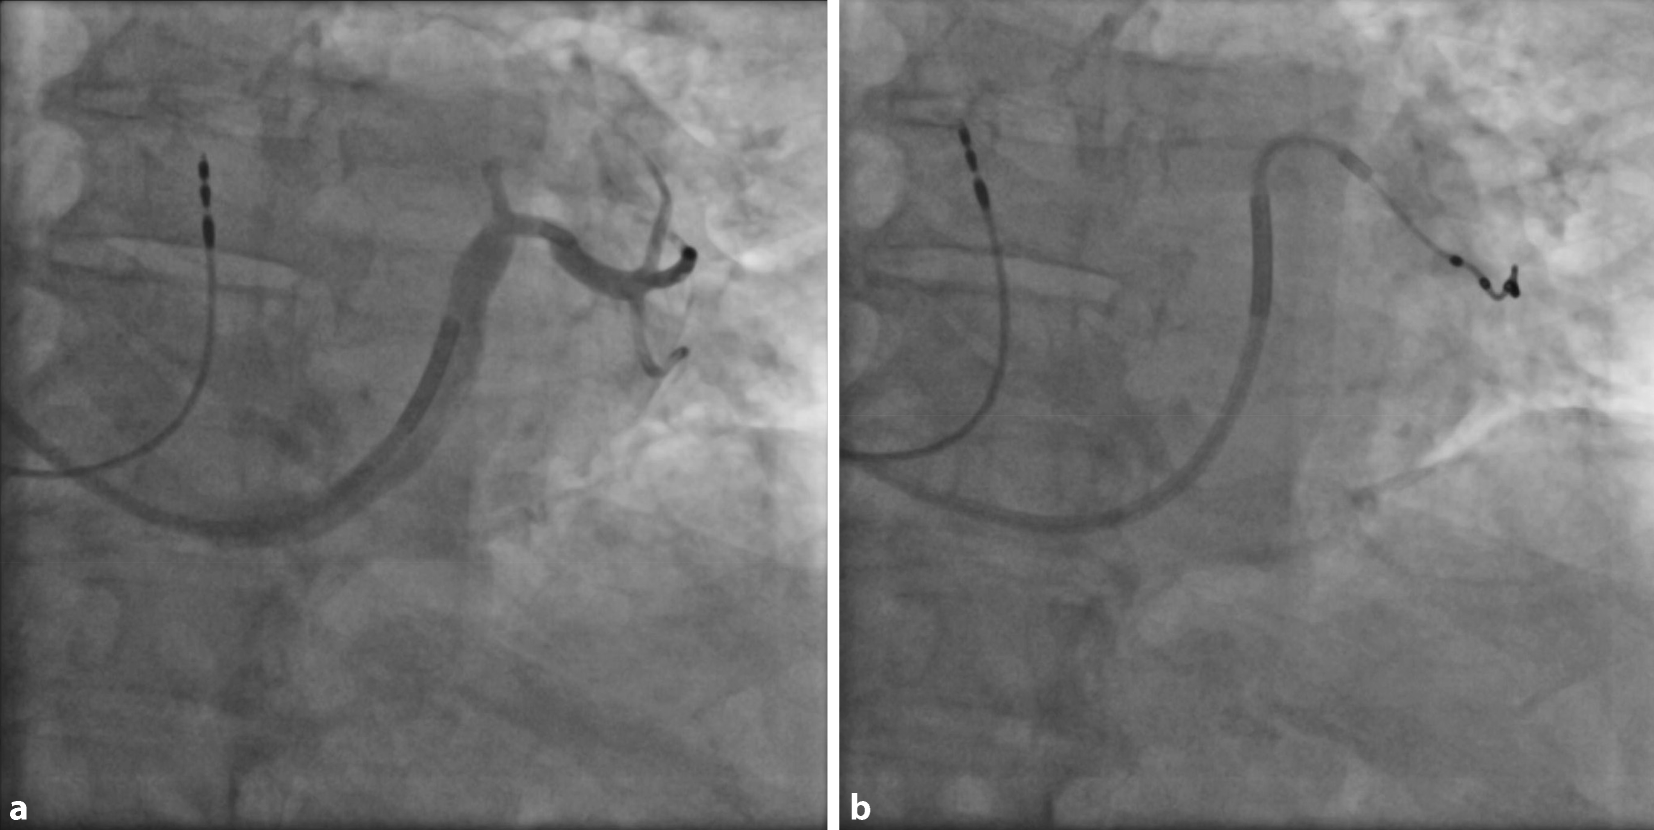

Postoperativ sollte eine PA- und laterale Röntgenaufnahme des Thorax gemacht werden, um die angemessene und stabile Position der LV-Elektrode zu bestätigen (Abb. 12). Außerdem sollte im Rahmen der ersten Nachsorge ein EKG aufgezeichnet werden, das die intrinsische Erregung, RV-Stimulation, LV-Stimulation und biventrikuläre Stimulation dokumentiert. Dies kann als Referenz z. B. für einen Stimulationsverlust der LV-Sonde herangezogen werden und zusätzlich Aufschluss über die Kammerkomplexbreite unter biventrikulärer Stimulation geben. Die RV/LV-Synchronität könnte hier optimiert werden, obwohl der klinische Nutzen im Vergleich zur AV-Zeit-Optimierung weiterhin fraglich ist (Abb. 13).

Abb. 12

Posterior-anteriore (a) und laterale (b) Röntgenaufnahme des Thorax, die eine gute Position der LV-Elektrode bei einer De-novo-CRT-D-Implantation zeigen